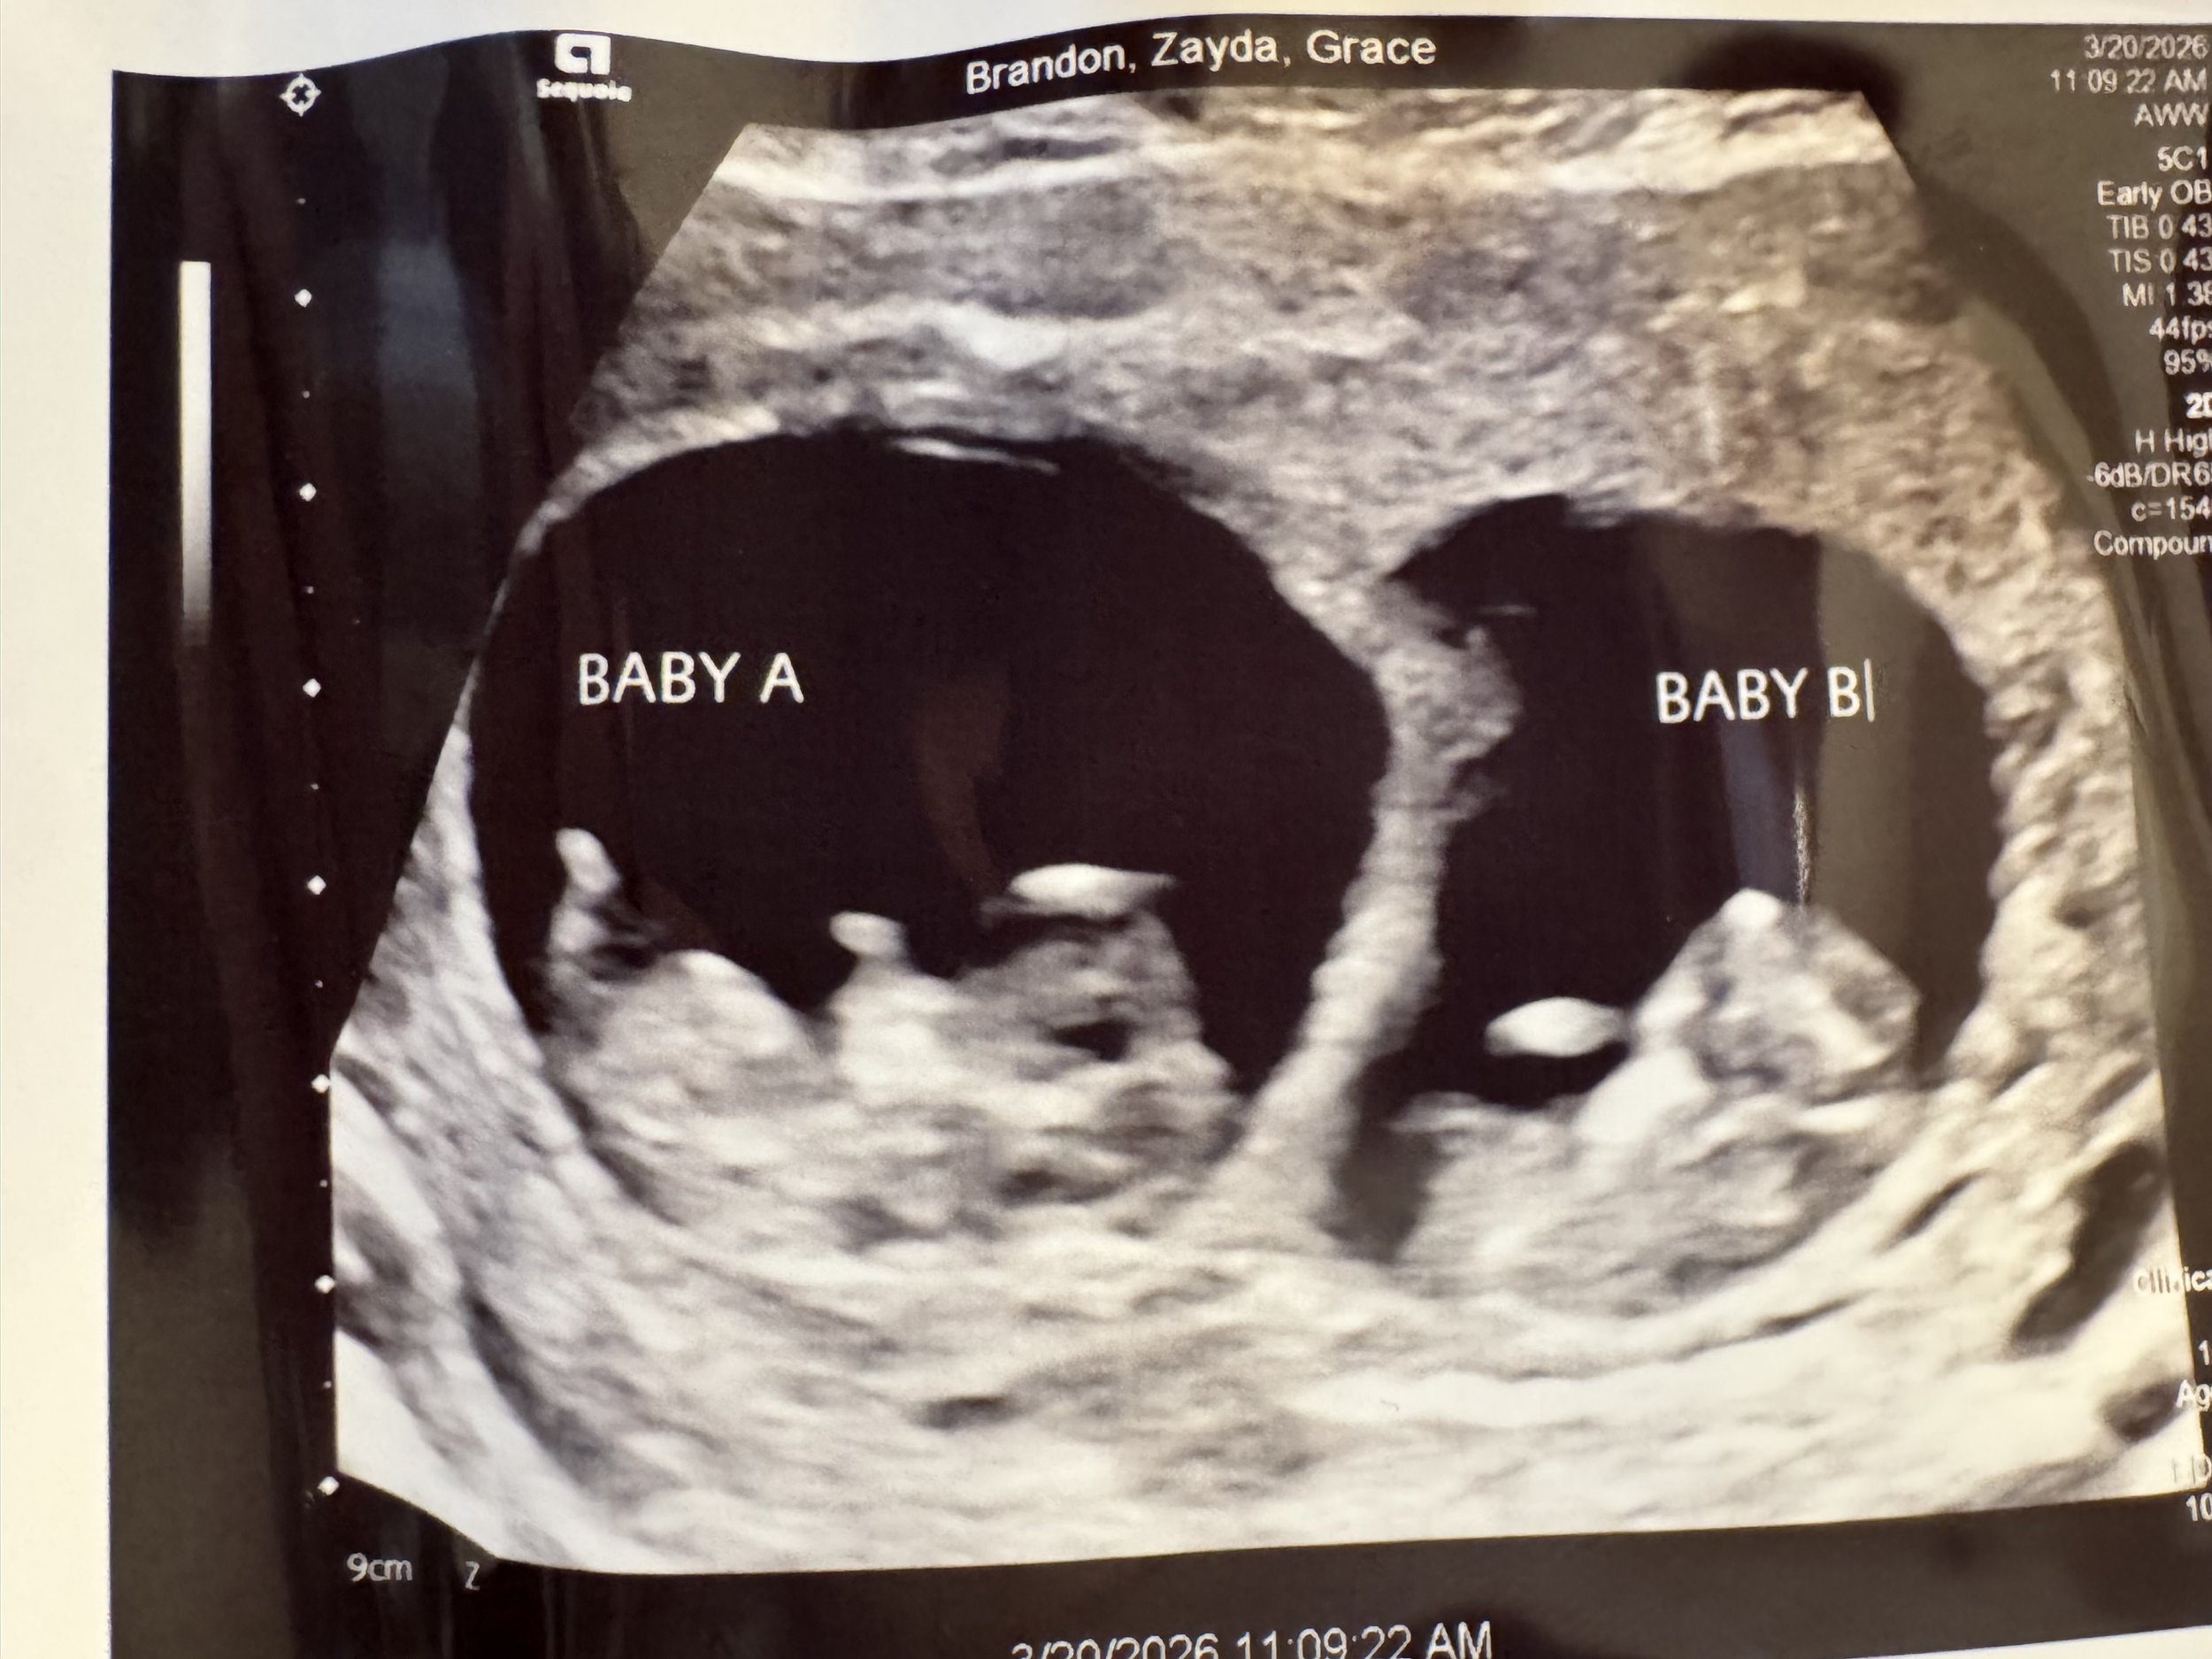

Cole and Zayda’s little TWO!

Grace and I are thrilled to welcome three more grandchildren coming this summer! Glory, our granddaughter to Roman and Isabelle will have 7 cousins born this year. God has blessed!